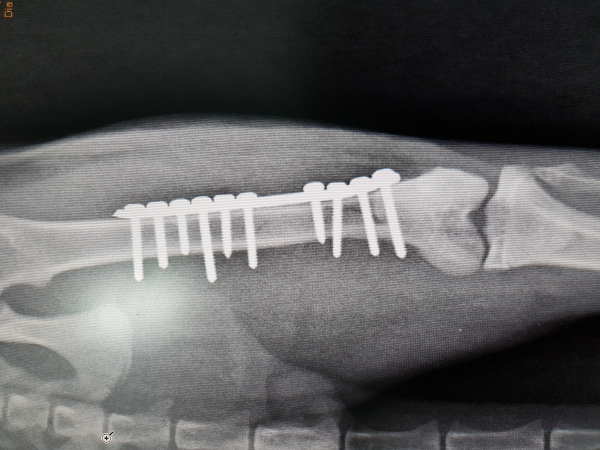

Con más de 20 años de experiencia en éste campo, el Dr. Esteban Spínola, Veterinario Jefe del Hospital Veterinario Atabal, está apuntado a dicha carrera desarrollando y actualizándose constantemente en las diferentes técnicas que esta especialidad exige.

Para ello, asiste a importantes y numerosos Congresos Nacionales e Internacionales y a los Grupos de Trabajo de Traumatología del Gevo de Avepa (Asociación de Veterinarios Especialistas en Pequeños Animales), de la que es miembro.